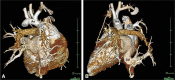

Methods: Between April 2011 and November 2018, 22 patients underwent scimitar vein surgery; 11 had baffling or reimplantation and 11 only had the new operation that included resection of the atrial septum with removal of the muscular limbus. The left atrium was pulled down toward the scimitar vein and a V-shaped incision made at the scimitar vein atrial junction with the space filled with a pulmonary homograft. If the scimitar vein coursed adjacent to the atrium, a V-shaped incision was made into the scimitar vein and directly anastomosed to the atrium. A patch of autologous pericardium was used to septate the atrium and an additional patch placed anteriorly to augment the inferior vena cava.